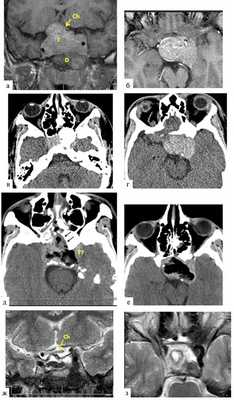

Юноша 14 лет. С раннего возраста опережал сверстников в росте, особенно рост ускорился в последние 3 года, появились симптомы несахарного диабета в виде жажды и полиурии. В 2007 и 2008 гг. у пациента произошли повторные переломы левой локтевой кости на фоне выявленной фиброзной дисплазии левых лучевой и плечевой костей. В ноябре 2015 г. выполнено оперативное вмешательство в связи с юношеским эпифизиолизом головки левой бедренной кости. Поводом для проведения магнитно-резонансной томографии (МРТ) головного мозга в 2015 г., в результате которого обнаружена СТГ-секретирующая аденома гипофиза, послужило снижение зрения (см. табл. 2, 3, рис. 1). Рис. 1. Клинический случай 1. а, б — картина, полученная при МРТ до операции; в, г — картина, полученная при СКТ до операции; д, е — картина, полученная при СКТ после операции; ж, з — картина, полученная при МРТ после операции. Т — опухоль; D — очаг фиброзной остеодисплазии; Ch — хиазма.

При обследовании в Национальном медицинском исследовательском центре нейрохирургии им. акад. Н.Н. Бурденко установлен следующий диагноз: акромегалия, активная фаза; аденома гипофиза; пангипопитуитаризм (вторичный гипотиреоз, гипокортицизм, гипогонадизм); несахарный диабет; синдром МакКьюна—Олбрайта; полиоссальная фиброзная дисплазия; хиазмальный синдром (см. табл. 2, 3).

Нами произведено эндоскопическое эндоназальное транссфеноидальное удаление крупной эндо-супра-латеро (S)селлярной опухоли гипофиза. Выполнен двусторонний доступ к основной пазухе. Левая половина пазухи заполнена крупным оссификатом, переходившим на дно седла (рис. 2). Рис. 2. Клинический случай 1. Интраоперационные фотографии. а — кость, пораженная фиброзной остеодисплазией (fd), расположенная перед турецким седлом (м — слизистая полости носа); б — правая половина турецкого седла (s), обнаруженная после частичной резекции пораженной кости (fd); в — обе половины турецкого седла (s) после полной резекции пораженной кости (fd). Бором трепанированы кости дна седла. После рассечения твердой мозговой оболочки (ТМО) обнаружена гетерогенная ткань аденомы гипофиза замазкоподобной консистенции, и для ее удаления потребовались отсосы увеличенного диаметра. Постепенно, разделяя опухоль на фрагменты кюретками, удалось удалить опухоль отсосами практически полностью, в том числе и из латеральных отделов левого кавернозного синуса. Однако тонкие плотные пласты опухоли остались в нескольких местах на ТМО — отделить их не удалось. Из обоих крупных узлов — правого переднего и левого заднего — опухоль удалена. На фоне выведения ликвора в дренаж капсула опухоли расправилась, ликвореи не было. Учитывая, что к концу операции образовалась огромная полость с кровоточащими стенками и после нагрузочных тестов не выявлено ликвореи, решено вход в полость капсулы удаленной опухоли не закрывать.

Гистологическое исследование подтвердило наличие соматотропиномы с высоким уровнем маркера пролиферативной активности опухолевой клетки Ki-67 — 6—7% (см. табл. 4).

Послеоперационный период протекал без особенностей. Профилактически проводилось люмбальное дренирование в течение трех суток. Назальной ликвореи не было. В неврологическом статусе — без отрицательной динамики. После операции отмечено повышение остроты зрения левого глаза (см. табл. 3).

При контрольной спиральной компьютерной томографии (СКТ) выявлена картина практически полного удаления опухоли (см. рис. 1), при этом клинико-биохимической ремиссии акромегалии не было (см. табл. 2). Начата комбинированная терапия пролонгированными аналогами соматостатина и каберголином, на фоне которой сохранялись высокие уровни инсулиноподобного фактора роста 1-го типа (ИРФ-1) и СТГ. С учетом инвазивного характера опухоли и отсутствия ремиссии принято решение о проведении стереотаксической лучевой терапии.